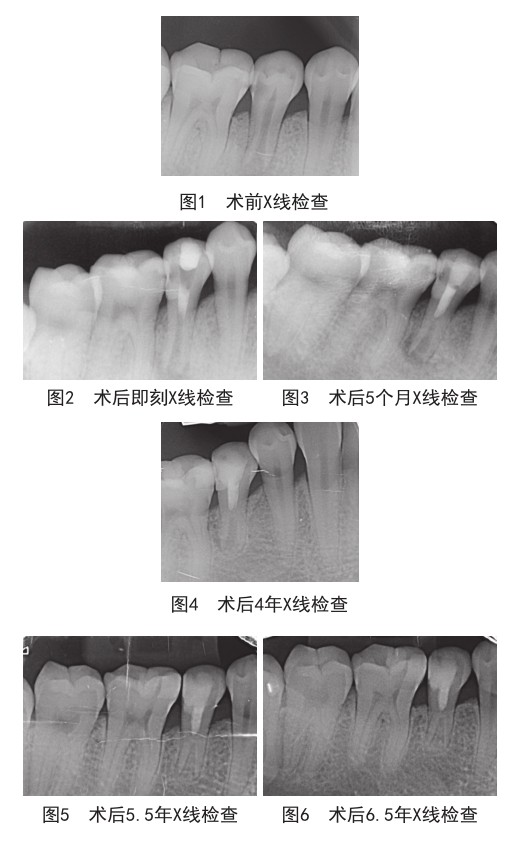

牙髓血运重建术治疗成人年轻恒牙慢性根尖周炎1例

牙髓血运重建术(dental pulp revascularization)是一种适用于牙髓坏死或慢性根尖周炎年轻恒牙的治疗方法,在临床症状的减轻方面不仅同根尖诱导成形术或根尖屏障术具有相同疗效,并且具有促进牙根增长、根管壁增厚及根尖孔闭合等特点,在年轻恒牙慢性根尖周炎的青少年患者中运用已取得了较满意的治疗效果[1,2],但对于罹患相同疾病的成人行牙髓血运重建术相关报道和相应的组织学研究较少见。(剩余5355字)